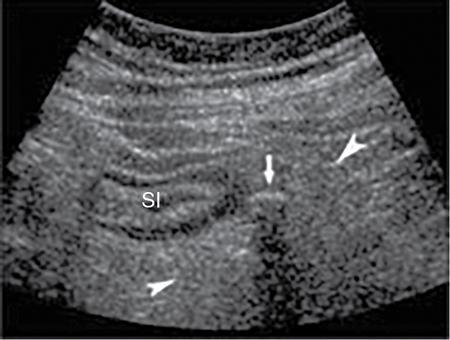

Ultrasonography (USG)